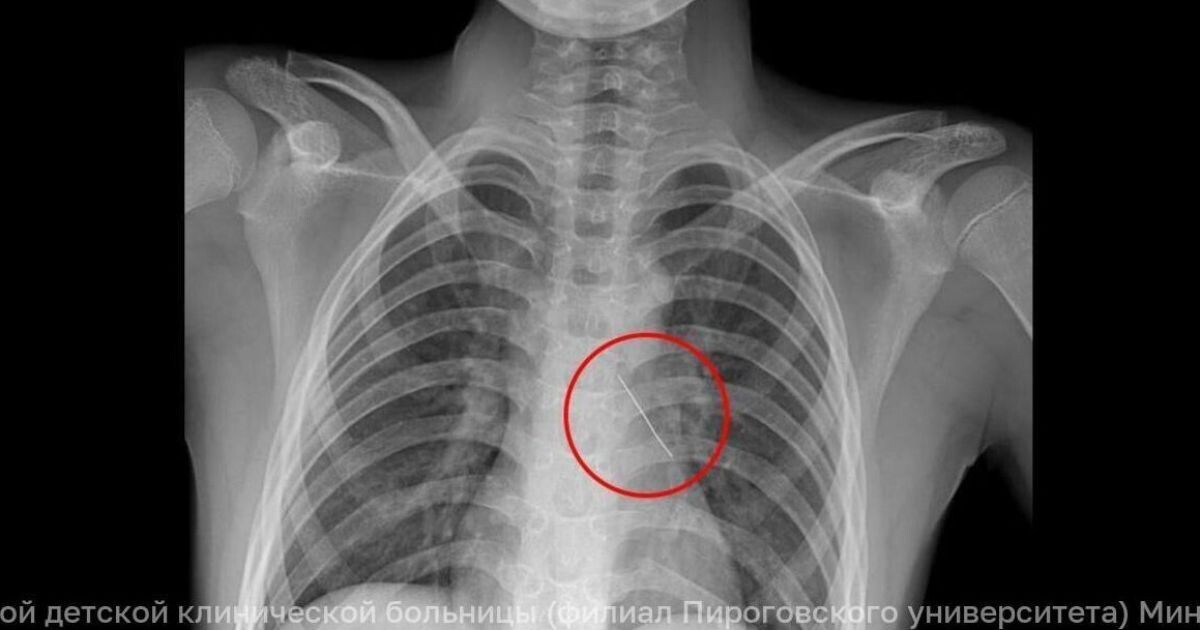

Вдохнул изогнутую булавку: 11-летнего калининградца спасали московские хирурги

11-летний мальчик вдохнул французскую булавку, которая пробила бронх. Местные врачи не смогли помочь, и ребенка срочно доставили в Москву. Что сделали хирурги и как он себя чувствует сейчас — в материале.